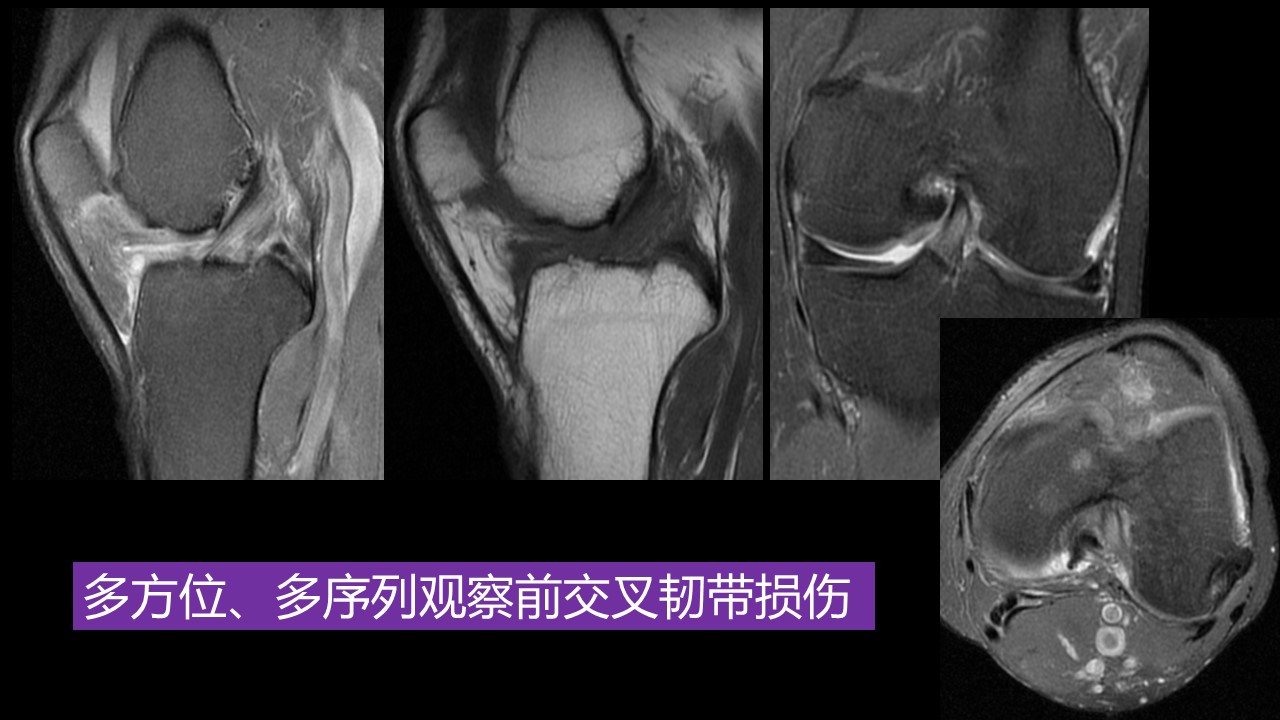

“膝关节损伤:MR图像解读,影像与诊断PPT” 的相关文章